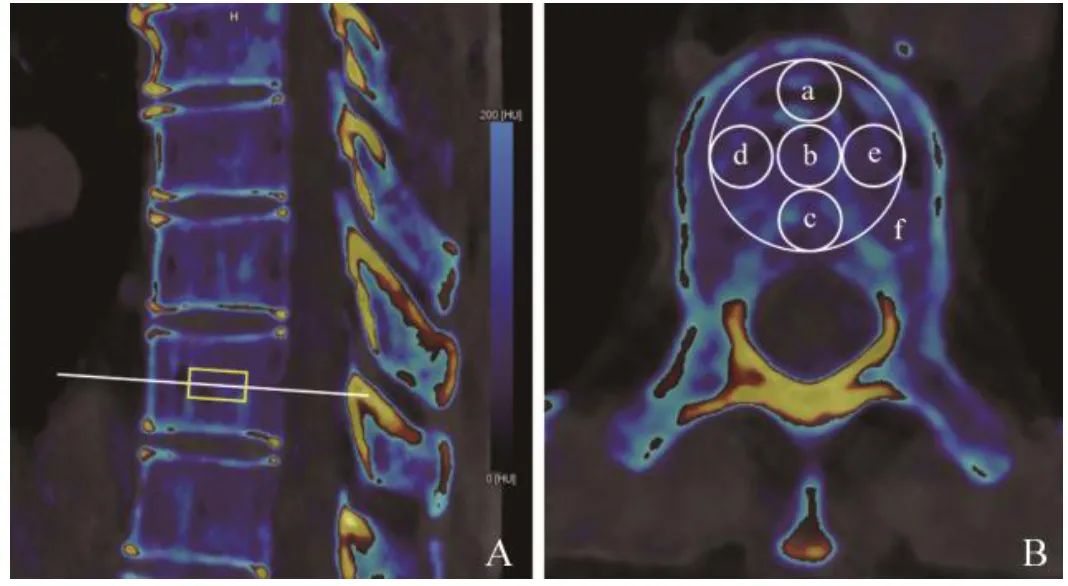

全能谱序列图像传至西门子Syngo.via B60后处理工作站,在Dual-Energy工作流中选择肝脏虚拟平扫对图像进行后处理分析,通过修改双能量肝脏虚拟平扫配置参数,将碘的斜率修改为钙的斜率(厂家预设参考值为1.55@120 kV),为更准确地获取钙物质分离,关闭碘的线束硬化校正算法。在横断位上选取T7~T12椎体中间层面(通过椎体上下终板中点的横断层面)松质骨区域勾画感兴趣区(ROI),层厚5 mm,将十字定位标记放在椎体中心(通过椎体前后缘及左右缘中心点),分别于椎体前、中、后、左、右勾画ROI(图1),设置固定ROI面积为(0.3±0.1)cm2,再对椎体勾画整体ROI,面积≥1 cm2,ROI尽可能多地包含松质骨,避开皮质骨、椎后静脉丛、骨岛。各椎体测量参数包括钙的CT值(contrast media,CM)、钙浓度(calcium density,CaD)、虚拟单能70 keV CT值(ME70)、虚拟平扫值(virtual non-contrast,VNC)、脂肪分数(fat fraction,Fat)。所有测量由2名观察者独立完成,其中1名观察者在3个月后重复测量VCI各参数。同时记录CT扫描的容积剂量指数和剂量长度乘积,均由机器自动给出。

图1  椎体VCI参数测量。A.矢状位示椎体ROI放置层面;B.轴位VCI图像ROI勾画,a~f分别对应前、中、后、左、右和整个椎体ROI。整个椎体VCI参数:钙的CT值90.5 Hu,钙浓度3.4 mg/cm3,虚拟单能70 keV CT值83.2 Hu,虚拟平扫值-8.3 Hu,脂肪分数38.1%